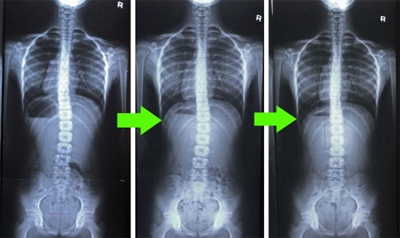

척추측만증은 척추의 변형으로 허리가 C자 또는 S자로 휘어져 골반이나 어깨의 높이를 차이 나게 만드는 질환이다. 보통 성장기 소아 청소년들에게 원인을 알수 없이 많이 발생하지만 의자에서 생활이 많은 요즘은 성인들에게도 발생빈도가 높아지고 있는 추세다. 한번 휘어진 척추는 성장기 동안 키가 크는 과정에서 그 각도가 점점 심해지게 돼 근골격계와 신경계통의 틍증을 일으키는 것은 물론 청소년들의 가장 큰 고민 중 하나인 작은 키의 원인이 될수 있다. 이렇다 보니 수험생들 중에는 수능시험 후 미뤘던 척추측만증 치료를 받으려는 이들이 많다고 한다.

척추측만증은 심한 경우나 급속히 진행될 경우 수술적인 치료를 고려할 수 있지만 수술과정과 수술 후 회복 및 재활과정, 수술후유증 등을 생각하면 비수술적인 치료가 권장된다. 측만이 유연하고 측만 각도가 20~40도라면 보조기 치료가 더 효과를 볼 수 있는 것이다. 척추의 성장을 허용하면서 만곡을 교정하고, 환자의 성장이 완료될 때까지 교정을 유지해 만곡의 진행을 막아주기 때문이다. 그러나 보조기 역시 어린나이에 착용을 해야되며 수동적인 개념이기 때문에 한계가 있을수 있다. 보통 어린 나이일수록 교정 효과가 좋으며, 척추측만증 전문병원에서 전신 체형분석 및 생체역학적 족부스캔검사, MFT 컴퓨터밸런스 검사 등 본인의 측만 정도를 정확하게 측정한 후 맞춤 척추교정 및 강화 운동처방 프로그램과 생체역학적 맞춤발보조기깔창 처방을 병행하면 몸의 변화를 느낄 수 있다.